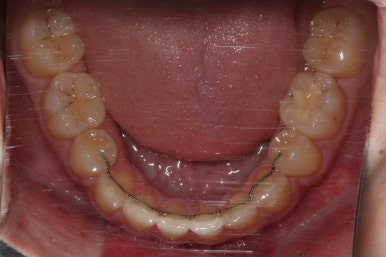

이제 치료가 끝났습니다.

매우 치아가 가지런해졌고, 당연히 덧니는 해소가 되었으며 맞물림도 굉장히 좋아졌습니다.

다른 분드로가의 차이점은 치료 종료 후 유지장치를 할 때 앞니만 하는 것이 아니라 발치한 자리가 다시 벌어지지 말라고 약간 연장해서 유지장치를 부착해 주게 됩니다.